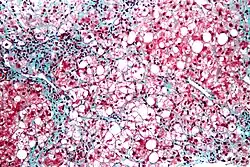

Micrograph showing a fatty liver (macrovesicular steatosis), as seen in metabolic dysfunction–associated steatotic liver disease. Trichrome stain.

The fatty change represents the intracytoplasmatic accumulation of triglycerides (neutral fats). At the beginning, the hepatocytes present small fat vacuoles (liposomes) around the nucleus (microvesicular fatty change). In this stage, liver cells are filled with multiple fat droplets that do not displace the centrally located nucleus. In the late stages, the size of the vacuoles increases, pushing the nucleus to the periphery of the cell, giving a characteristic signet ring appearance (macrovesicular fatty change). These vesicles are well-delineated and optically "empty" because fats dissolve during tissue processing. Large vacuoles may coalesce and produce fatty cysts, which are irreversible lesions. Macrovesicular steatosis is the most common form and is typically associated with alcohol, diabetes, obesity, and corticosteroids. Acute fatty liver of pregnancy and Reye's syndrome are examples of severe liver disease caused by microvesicular fatty change.[20] The diagnosis of steatosis is made when fat in the liver exceeds 5–10% by weight.[14][21][22]